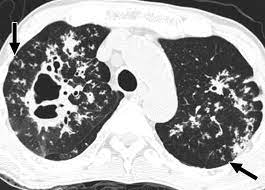

Computed tomography (CT) imaging has played a role in the evaluation and management of COVID-19, caused by the SARS-CoV-2 virus. However, it’s important to note

Computed tomography (CT) imaging plays a significant role in the diagnosis and evaluation of tuberculosis (TB), a bacterial infection caused by Mycobacterium tuberculosis. TB primarily